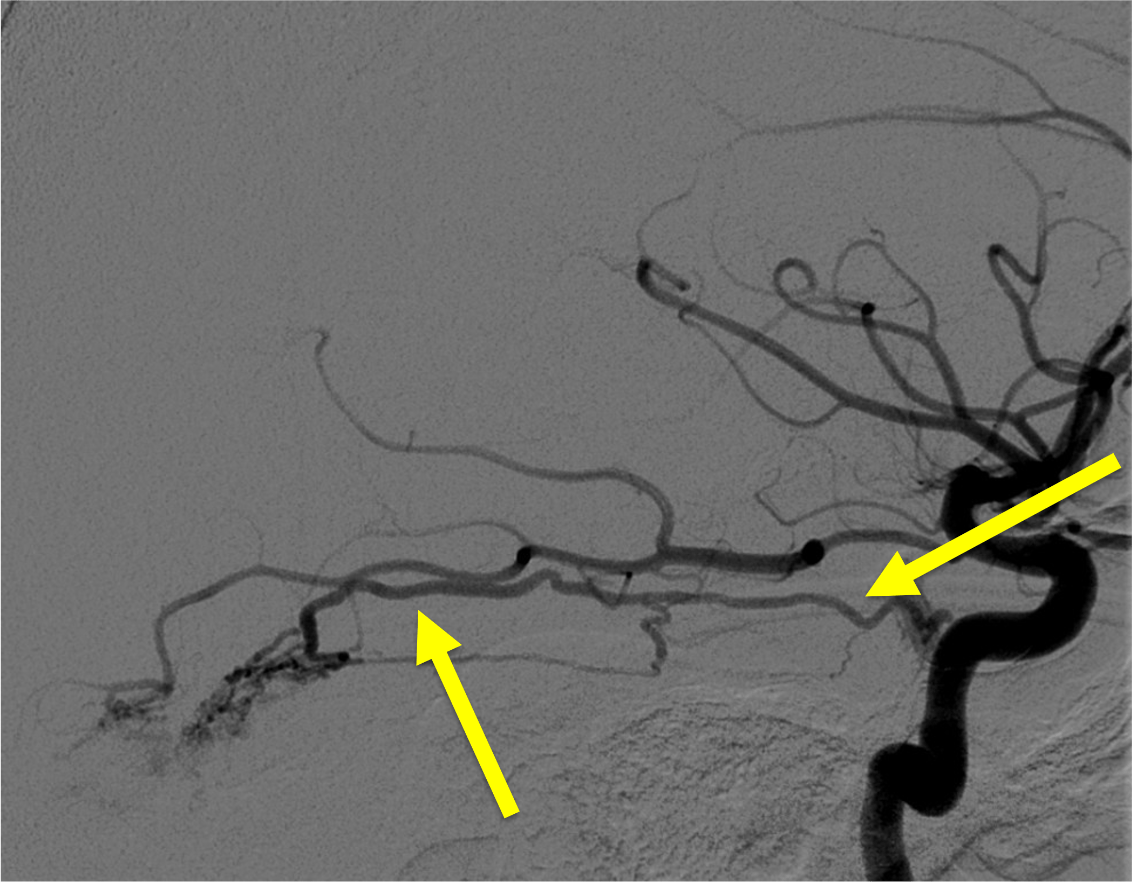

On this lateral view L ECA injection, name the vessel at the white arrow, which is the route of collateral between the ECA and ICA (yellow arrow) in this patient with longstanding ICA occlusion.

White arrow is the Ophthalmic artery-- here, likely collaterals from the ECA (through the internal maxillary artery --> ethmoidal artery) collateralize with the ICA through retrograde filling of the Ophthalmic